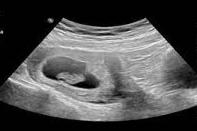

b超照片怀孕初期图片

b超照片怀孕初期检查的内容包括子宫的大小和位置,宫腔内是否能看到孕囊和孕囊的大小,囊内是否能看到卵黄囊、胎芽和胎心,双侧附件是否有异常回声。

一般怀孕40天左右看到卵黄囊是正常的。怀孕6周后,可以看到胎心和胎芽,就可以测量出胎芽的大小。